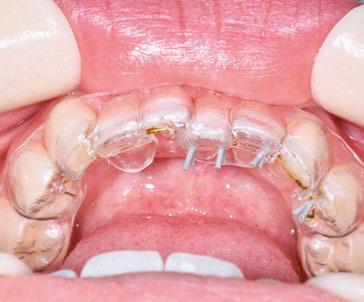

Figure 2: Initial lower occlusal

Figure 1: Initial center photo

This case involves a 13-year-old female patient with a complex malocclusion that includes multiple dental and skeletal issues. During the initial consultation, clinical evaluation showed severe maxillary crowding along with generalized spacing in the mandibular arch. The patient’s occlusal relationships were asymmetric, with a Class I molar relationship on the right side and a Class II molar relationship on the left. Notably, an anterior crossbite was observed, further complicated by a narrow, V-shaped maxillary arch — a common presentation that often exacerbates anterior-posterior discrepancies and limits functional occlusion. The patient also demonstrated poor oral hygiene, which is a key indicator of an indirect bonding system that does not reduce excess flash. ODB is superior in flash reduction, by being able to remove excess adhesive from three sides of the bracket instead of competitors who only remove adhesive from one side of the bracket. The presence of adhesive around brackets contributes to surface roughness which leads to plaque accumulation.1 Flash reduction will be very important for every patient’s orthodontic success (Figures 1-3).

The initial bonding appointment was completed efficiently within 35 minutes, including a comprehensive session on oral hygiene instructions and home care practices. Efficient time management at this visit allowed for strong patient education and engagement, factors that contributed positively to overall treatment adherence and outcomes.